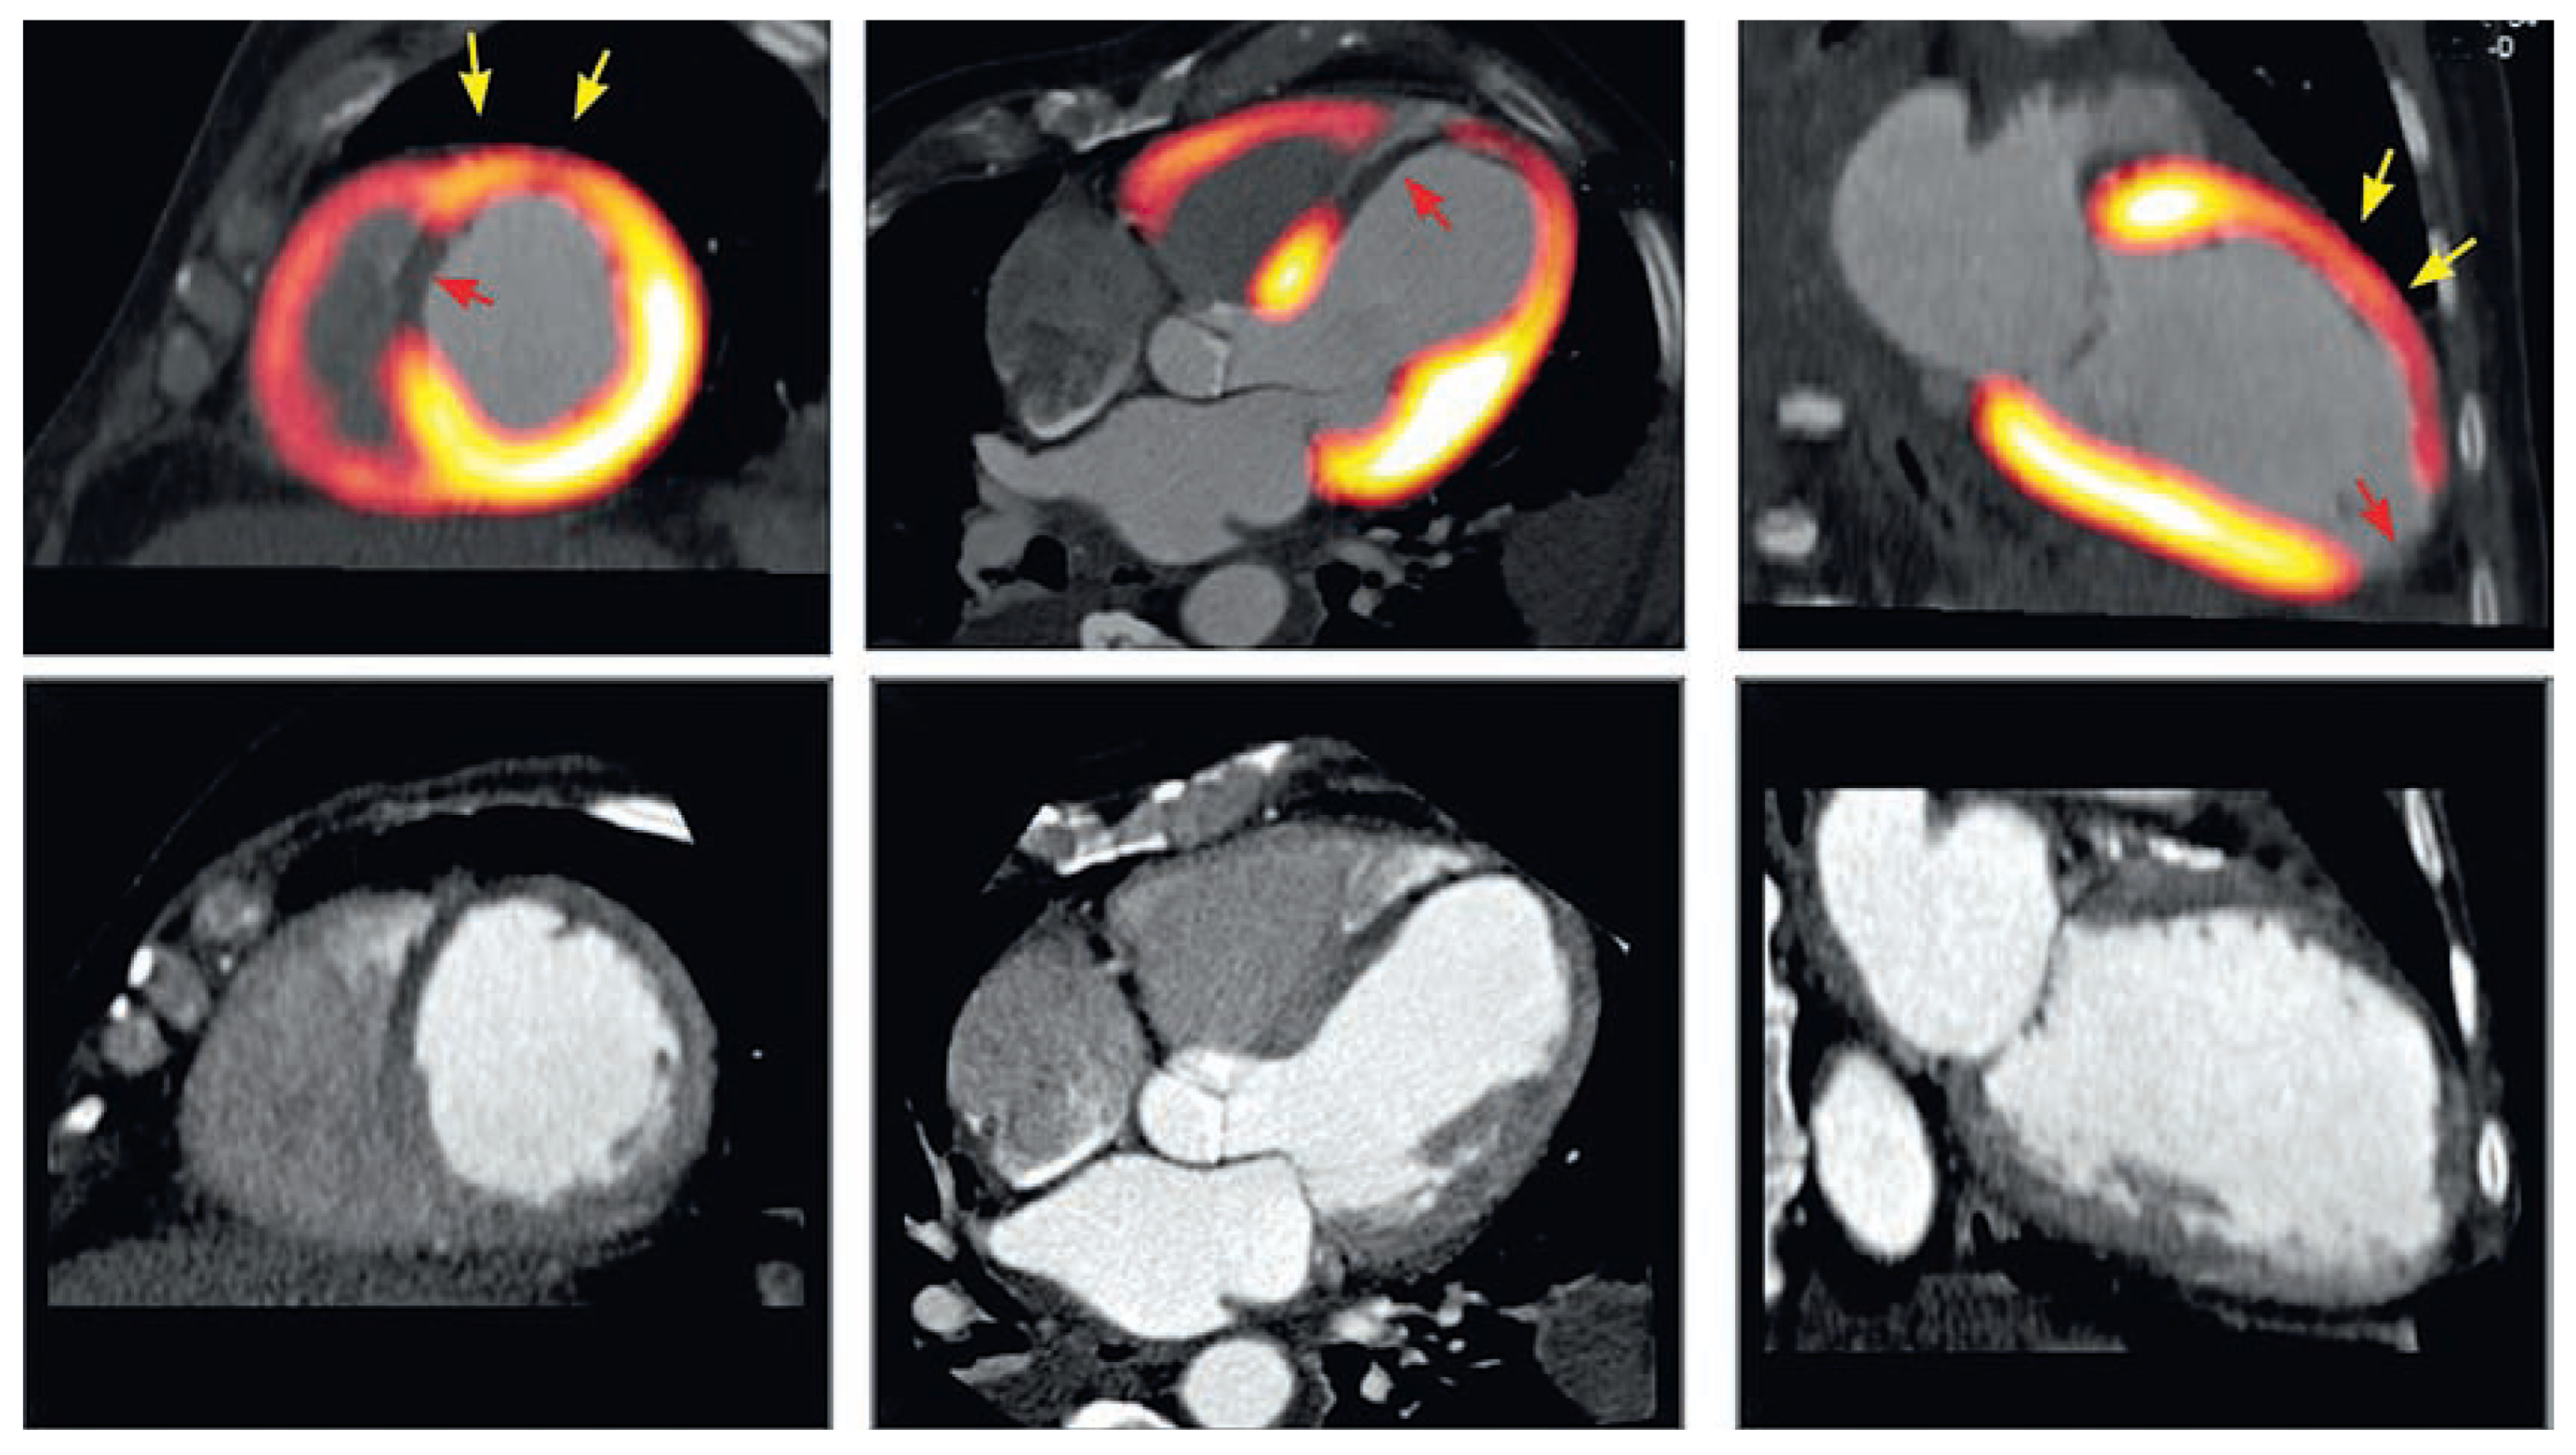

Figure 5.

Hybrid PET/CT images of the heart provide additional information on myocardial viability allowing differentiating segments with residual viable tissue (yellow arrows) from non-viable scar tissue (read arrow) in areas of myocardial infarction identified on CT images with significant wall thinning and hypokinesis (bottom row).

While extensive research over the past decades has shown the advantages of PET imaging over other diagnostic techniques, its widespread clinical use was limited by the limited availability of PET scanners and their relatively high cost. With the advent of hybrid scanners combining multidetector CT and PET scanners in one single machine, it is possible today to combine the anatomical information of coronary CT angiography with myocardial metabolism and perfusion from PET images in a single examination. These combined imaging devices open new perspectives on alternative clinical pathways for evaluating patients with CAD.